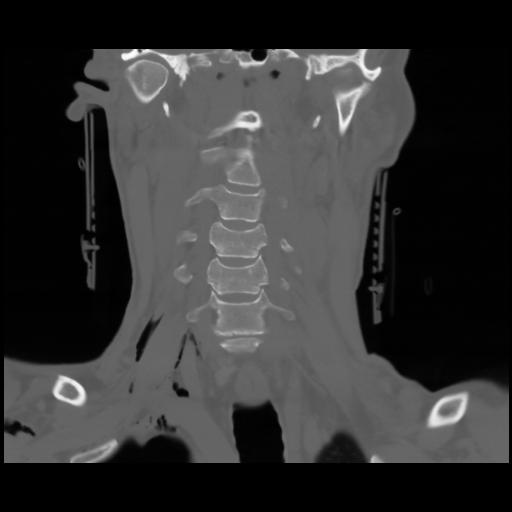

13 P.BLANDAS,,Coronal,2.000,P.BLANDAS,Coronal,